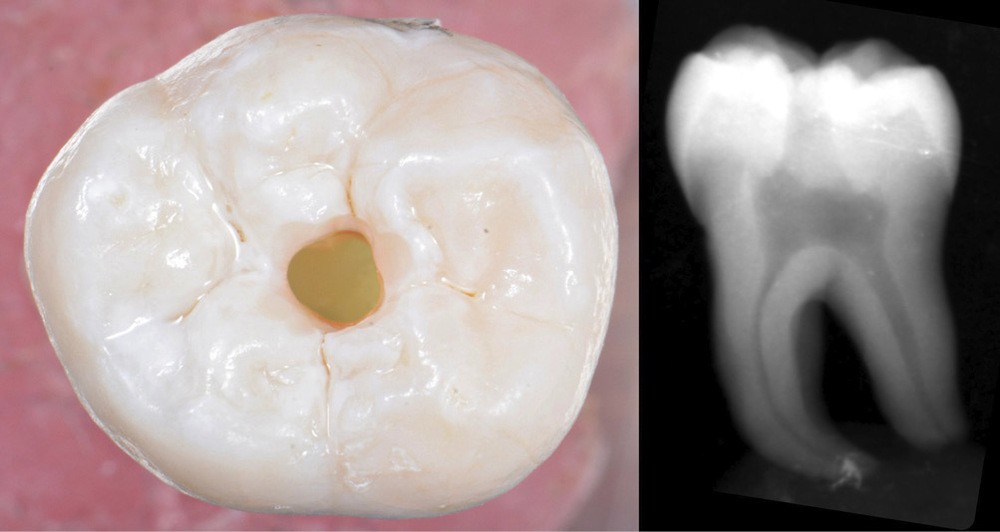

Aussi petite que possible, aussi large que nécessaire

Une cavité d’accès moderne, dictée par l’anatomie et la pathologie de la dent, optimiserait à la fois les pronostics endodontiques et biomécaniques et donc la longévité de la dent sur l’arcade (patient-centered dentistry ou dentisterie centrée sur le patient) (fig. 5).